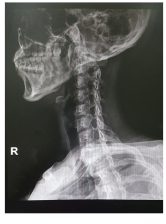

목디스크 증상 원인 치료방법 등 목 디스크 관련 정보에 대해 알아보도록 하겠습니다. 목 디스크는 목 뒤의 척추와 척추 사이에 있는 디스크라는 쿠션 역할을 하는 조직이 탈출하거나 파열되어 신경이나 척수를 압박하는 질환입니다.

1. 퇴행성 변화: 나이가 들면서 목 디스크가 노화되거나 반복적인 움직임이나 잘못된 자세로 인해 퇴행하게 됩니다. 이러한 퇴행은 디스크를 약화시켜 디스크가 정상 위치에서 돌출되거나 튀어나오게 할 수 있습니다.